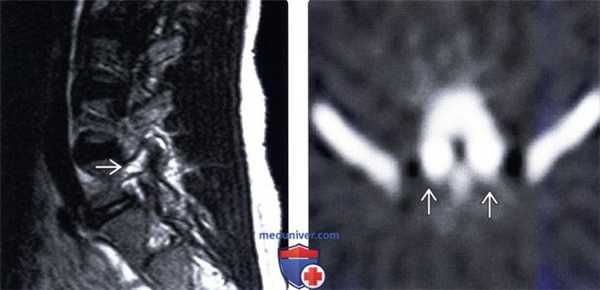

(Слева) Стрессовая реакция костной ткани в ответ на перегрузку межсуставной части дуги позвонка характеризуется усилением сигнала костного мозга корня дуги позвонка, межсуставной части дуги и суставного отростка, признаки этого видны на Т2-В14 в сагиттальной проекции. В последующем в этой зоне возник перелом.

(Справа) На ОФЭКТ-срезе пациента с двусторонним спондилолизом отмечается усиление захвата изотопа в области обеих МЧ дуг L5 позвонка.